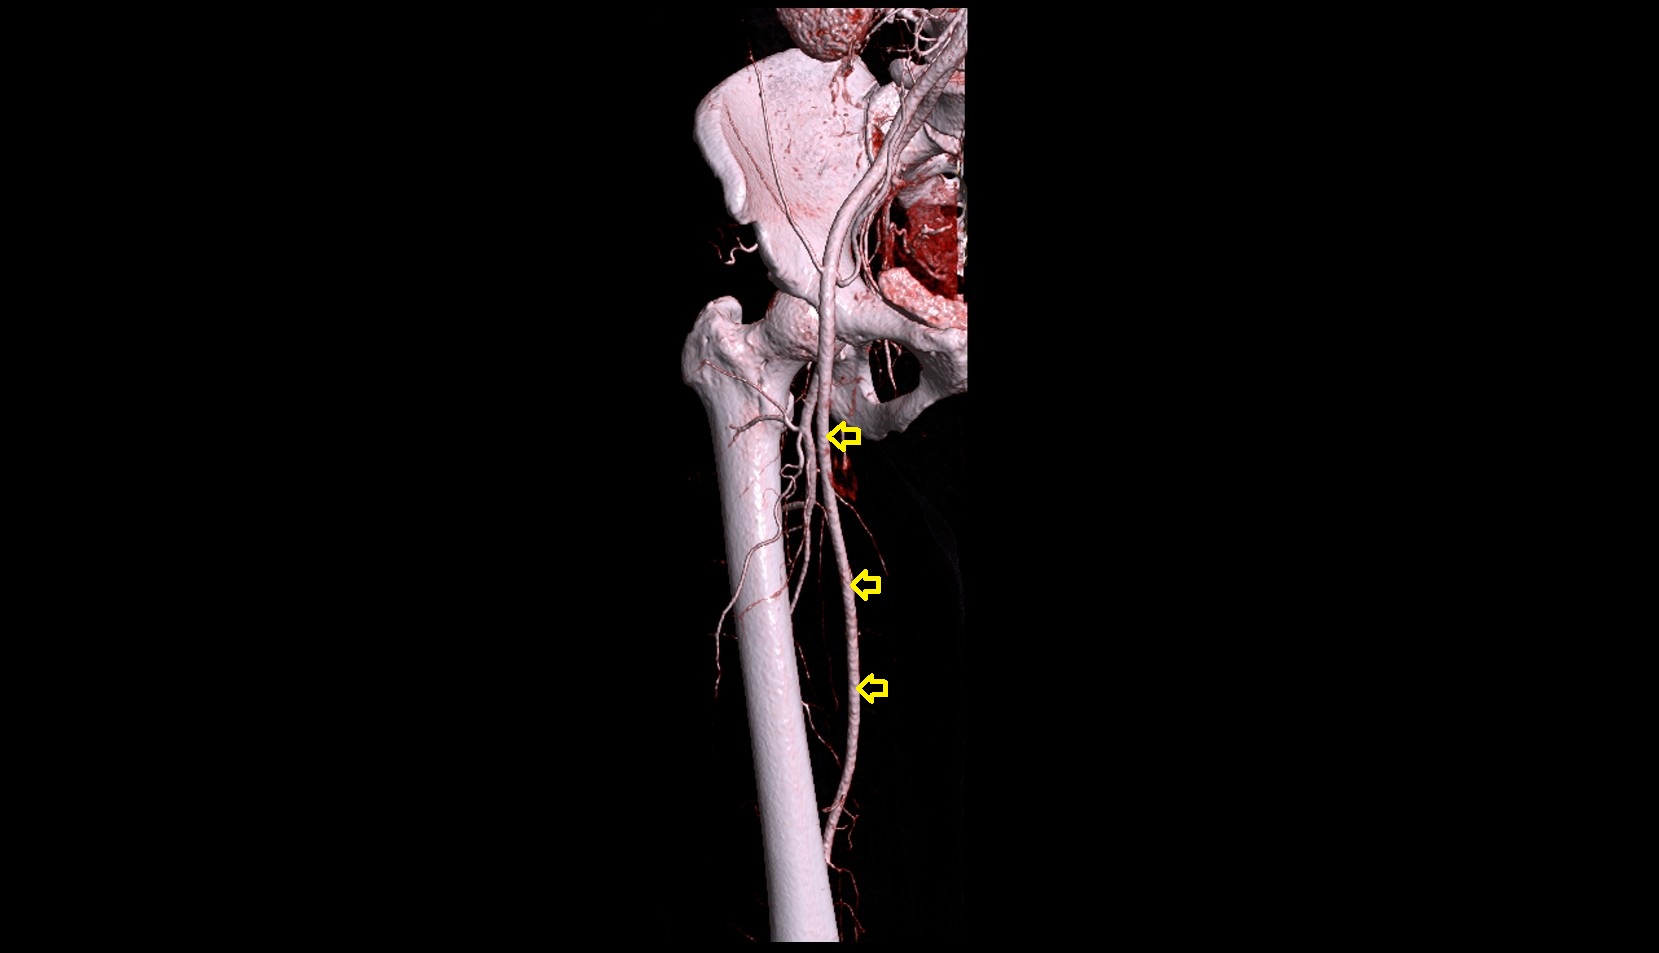

- Femoral artery

- Deep femoral artery (profunda femoris)

- Superficial femoral artery

- Lateral circumflex femoral artery

- Medial circumflex femoral artery